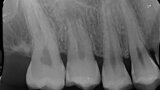

Fig. 3: Pre-op periapical radiograph.